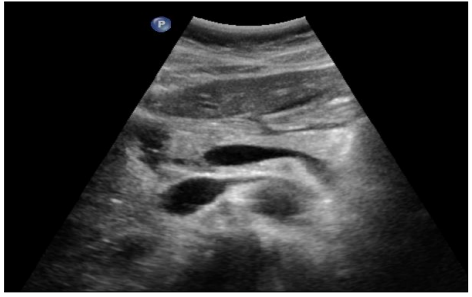

Cas cliniques - Secteur Abdomen

DRAGEAN AC & MEUNIER P. & PEZZULLO M. - UCL, ULG, ULB